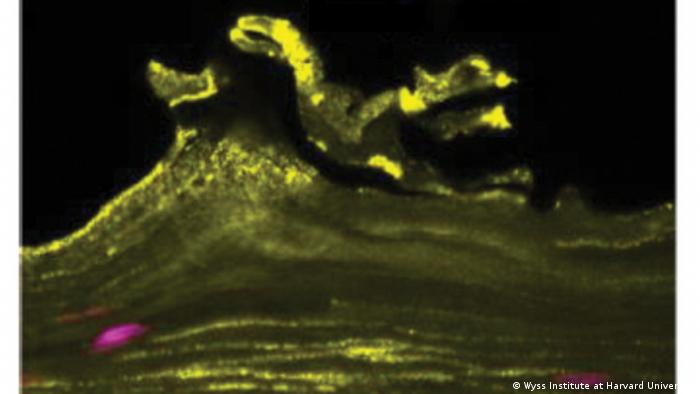

Un equipo de bioingenieros, entre ellos los del Instituto Wyss de la Universidad de Harvard, ha creado un modelo de "vagina en un chip"...